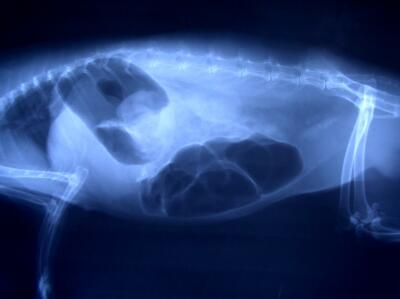

そして、一番恐ろしいのがこの「急性胃拡張」です。

腸閉塞→鼓脹症→急性胃拡張と進行するケースが多く、急性胃拡張にまで発展すると、命の危険がかなり高いため、緊急に何らかの処置が必要です。

写真の白く丸い影はすべて胃。

ここまで胃が膨らむと、他の臓器を圧迫して、機能をかなり阻害しています。

心臓が圧迫され血圧も下がり体温も低下。

うさぎ自身も激しい痛みを感じているため、まずは鎮痛剤の投与が必要です。

それから脱水を引き起こしているので、体液組成の調節のために皮下注射や点滴で電解質の補給を行います。

また、胃内のガスなどを取り除く必要があるため、口や鼻からチューブを入れて胃の内容物を吸引したり、場合によっては手術で閉塞を起こしている異物を取り除く処置が必要になります。

適切な治療を行ったとしても数時間から数日で死亡してしまうこともある恐ろしい病気です。